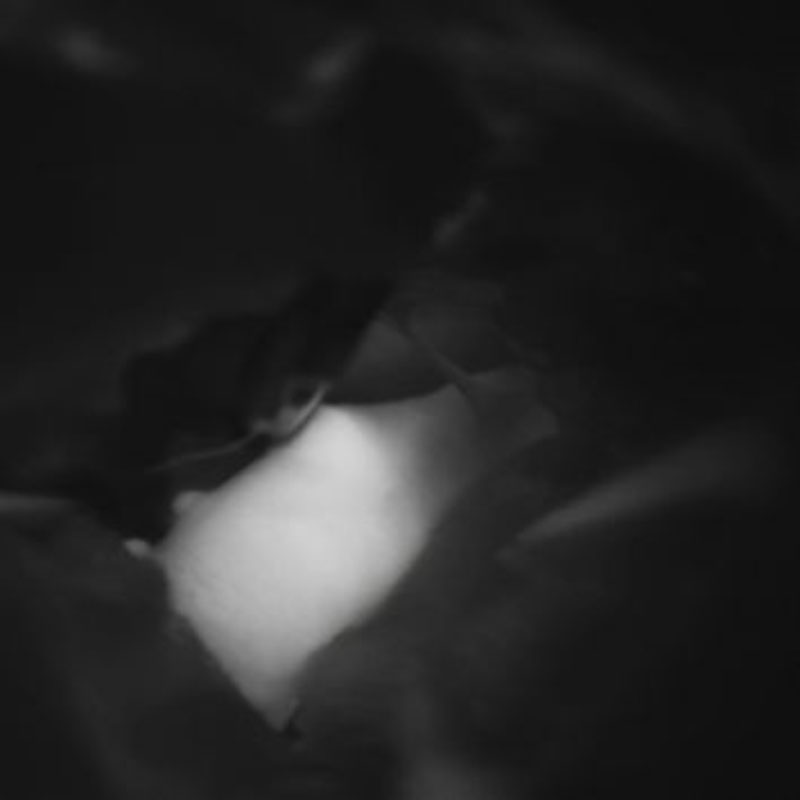

手術前

クリップ前

クリップ後

手術後

右中大脳動脈瘤

クリッピング術

術後血管撮影